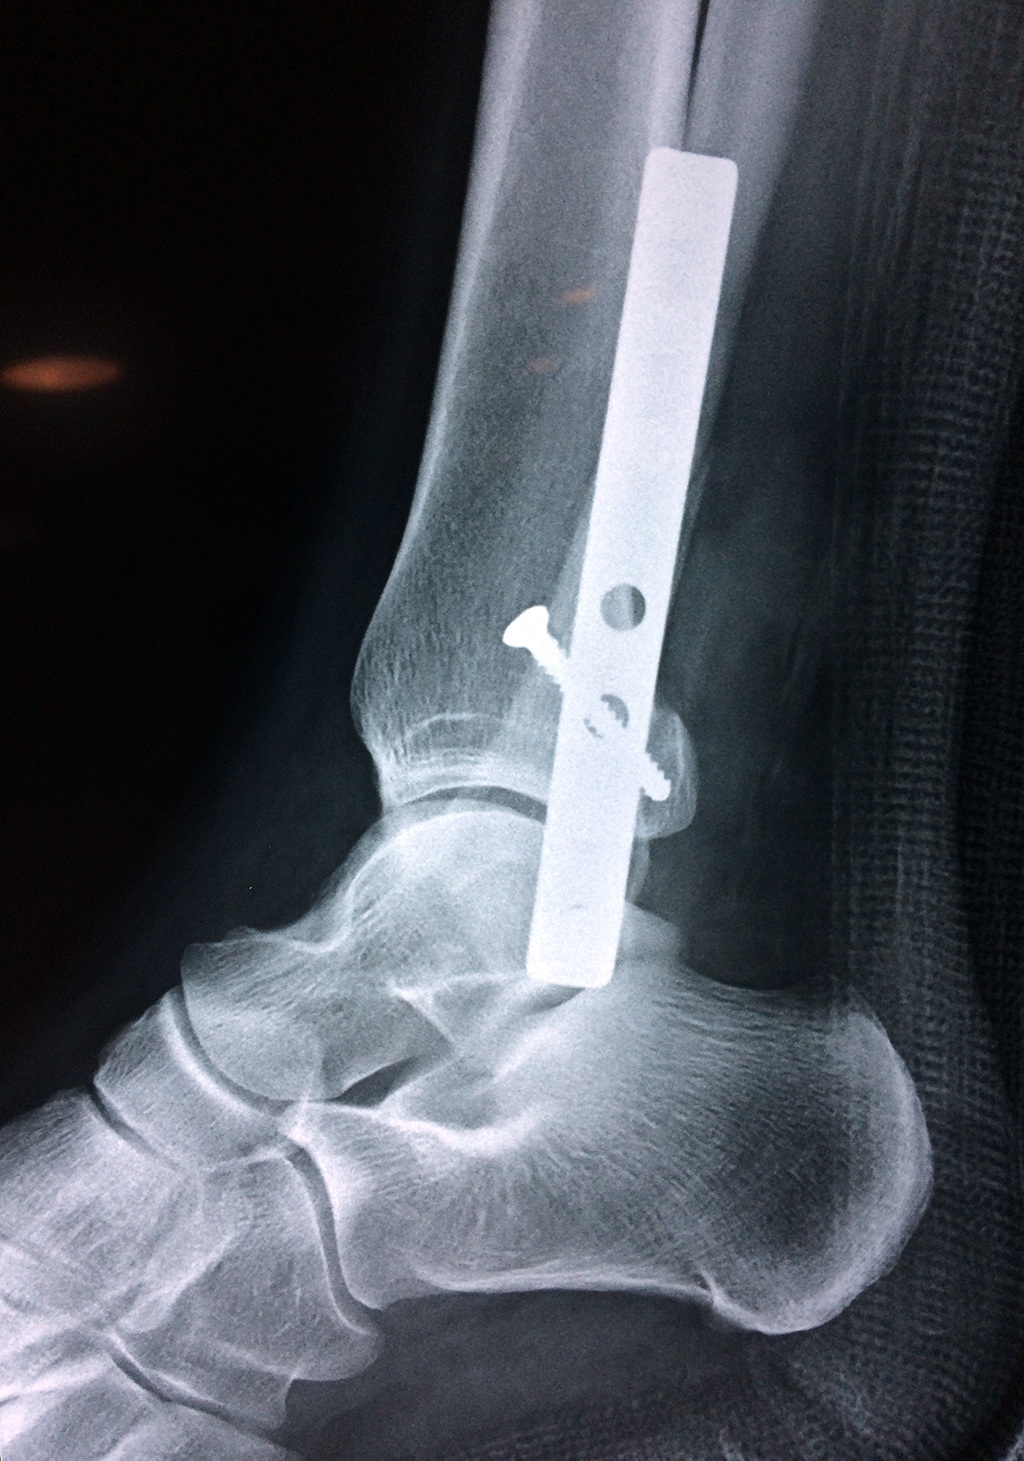

Cirugías de Peroné y Tibia

Cuando se necesita cirugía, es probable que esta implique el uso de clavijas de metal, tornillos o placas para sostener los huesos en su lugar mientras la fractura se consolida. Los elementos de soporte pueden ser temporales o permanentes.